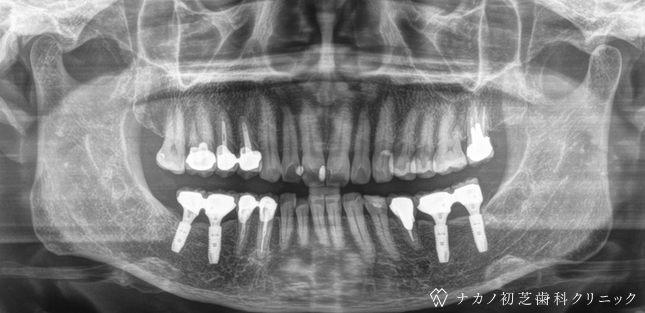

インプラント・7本 (70代男性)

-

BEFORE

AFTER

年齢 70代男性

治療内容 インプラント治療7本(骨造成の併用)

インプラント治療とは、歯を抜いた所にチタン製の人工歯根を埋入し、その上に歯を入れる方法です。骨を増やすことで、より審美的に治療が出来ました。費用 1本 400,000円(税込 440,000円)

リスク・副作用

腫れ・疼痛・違和感を感じるなどの症状を生じることがあります。